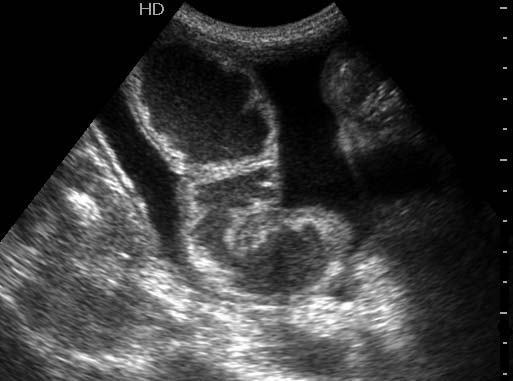

Мужчина средних лет с резкими болями в животе, тошнотой, рвотой.

Кишечная непроходимость. Можно предположить,странгуляционная.

Предположим - Расширенные петли кишечника , заполненные жидким содержимым на фоне свободной жидкости в брюшной полости

Типичная острая кишечная непроходимость, асцит.